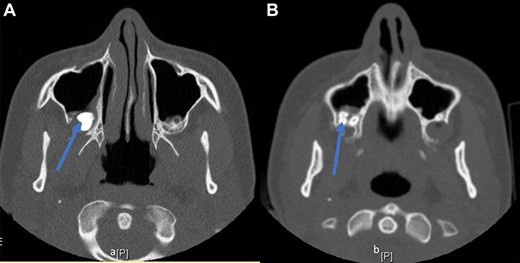

A 14-year-old female patient with no significant past medical history presented to our department 11 days following third molar extraction during which tooth number one was displaced into the right maxillary sinus cavity. A complete history and physical was performed. The patient was asymptomatic with postoperative changes along her gingiva, but the remainder of her exam was normal. There was no sinus tenderness reported on palpation or signs of sinusitis on endoscopy. A computed tomography (CT) scan of the sinuses without contrast was performed, which revealed the displaced molar within the posterior inferior maxillary sinus and a posterior maxillary wall defect (arrow, Fig. 1A and B).

(A, B) CT sinus images of a displaced third molar (arrow) into the posterior aspect of the maxillary right sinus.